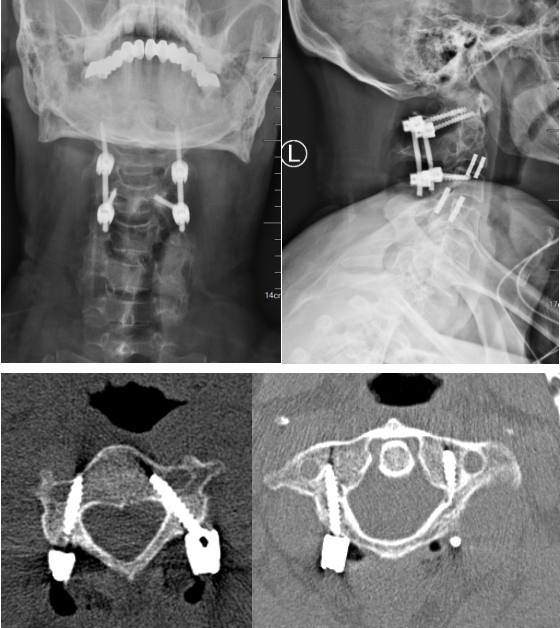

患者颈椎术后复查,置钉精准,内固定可靠